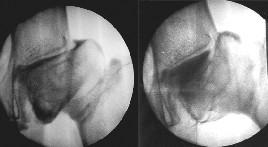

ARTERIOGRAFIA

A la izquierda cadera en addución observándose contacto entre cabeza femoral y cótilo. A la derecha en abducción observándose acúmulo de contraste por separación entre cabeza femoral y cótilo.